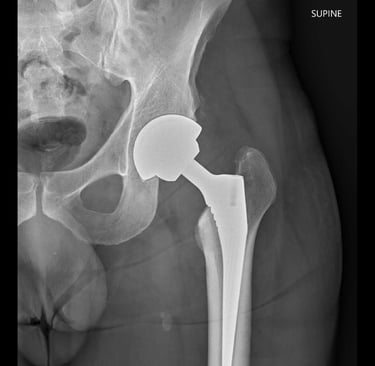

My neurosurgeon orders an X-ray of my hip.

The result isn’t vague. It isn’t “we’ll monitor it.”

It’s basically 100% certain: I need a hip replacement.

My first thought is brutally simple: I’m too young.

I’m 46 when I’m told. I turn 47 on 26 November.

Osteoarthritis sounds like one of those vague “getting older” diagnoses, but it’s actually pretty specific. It’s a type of joint wear-and-tear where the protective cartilage that helps bones glide smoothly starts breaking down. As that cushioning thins, the joint gets irritated and inflamed, movement gets stiff and painful, and the bones can start rubbing, or the joint mechanics can change in a way that makes everything worse. It’s bone on bone, and that’s not meant to happen.

In the hip, it can feel like deep pain, aching through the butt or thigh, stiffness after sitting, and a growing sense that walking is becoming work. When it gets severe enough, the “fix” isn’t more stretching or stronger painkillers; it’s replacing the joint surfaces entirely, which is exactly what a hip replacement does.